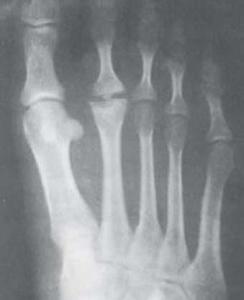

跖骨头骨软骨病是发生在跖骨头骨的无菌性坏死。多发生在15-16岁青少年,女性更常见。偶见于成年。坏死常发生在第二跖骨头,偶见于第三跖骨头。根据X线检查,可分为早、中、晚三期:早期表现为跖骨头骨骺致密,边缘不齐;中期为骨骺碎裂,关节间隙增宽;晚期关节腔变窄,变平,骨质硬化,关节内有游离体,出现退行性关节病变。